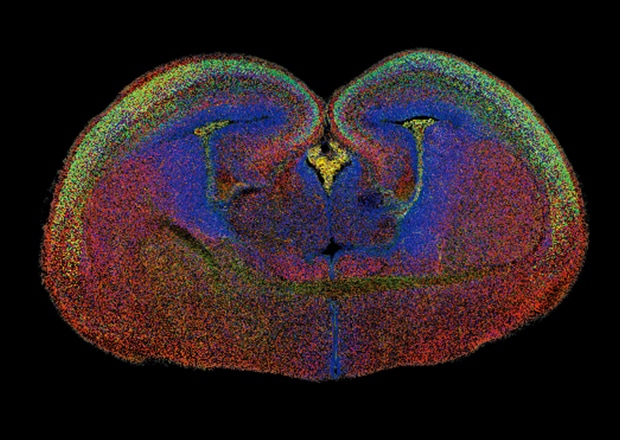

Figure 3-3: BZ's stitched image of a whole brain with multi-color fluorescence labeling